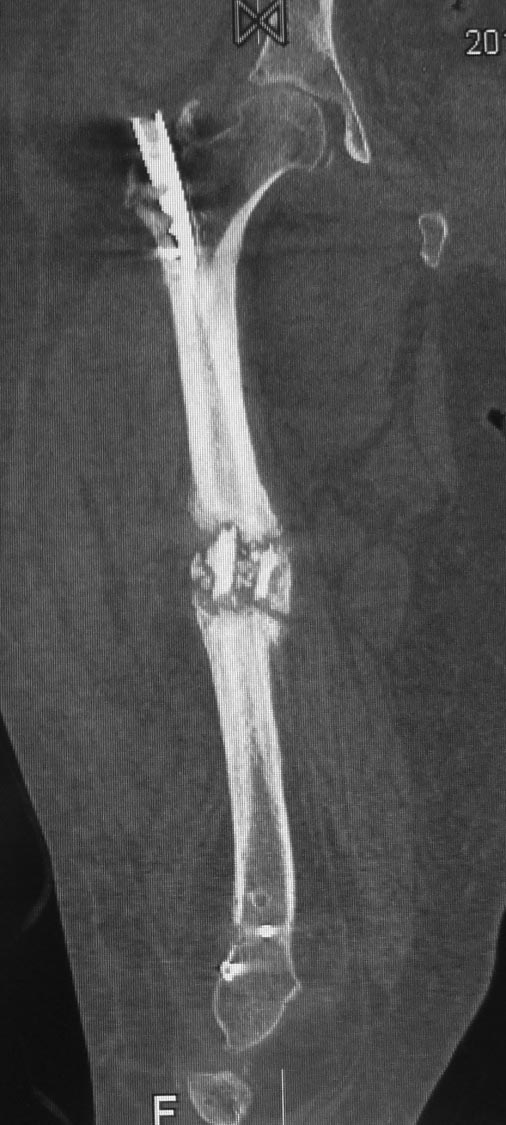

Уважаемые коллеги. Хотелось бы выслушать мнения и советы по представленному случаю. Пациент 42 лет, вес 130 кг, рост около 160 см, сахарный диабет в легкой форме (впервые выявлен после травмы). Травма в феврале 2011 г. - упал с мотоцикла на отдыхе за рубежом. По возвращении в Россию был прооперирован в несколько этапов: в марте 2011 г. - остеосинтез обеих костей правого предплечья пластинами по поводу открытого перелома; интрамедуллярный остеосинтез правого бедра; остеосинтез проксимального конца правой большеберцовой кости. В апреле 2011 г. был доставлен 1 блокирующий винт в дистальное отверстие гвоздя и выполнена пластика крестообразных и наружной боковой связок левого коленного сустава. В феврале 2012 г. были удалены фиксаторы с проксимального конца правой большеберцовой кости и выполнена пластика крестообразных и наружной боковой связок правого коленного сустава. За это время пациент смог начать ходить, сначала с костылями, а затем - без дополнительной опоры. Летом 2013 г. решил укрепить ноги с помощью подъемов пешком на пятый этаж. В результате - усталостная рефрактура правого бедра и перелом интрамедуллярного гвоздя. 09.09.2013 - реостеосинтез латеральным бедренным гвоздем с пластикой костной аутостружкой + СhronoS. Сейчас, через 6 мес после операции, может ходить без дополнительной опоры, периодически беспокоит болезненность в области правого бедра. На сегодняшних КТ - отсутствие признаков консолидации. Нужно ли что то делать и, если да, то что? Рассматриваемые варианты: повторная костная пластика дефекта; доставить блокирующие винты (самый проксимальный винт был удален через 3 мес после операции). Еще раз менять гвоздь не хотелось бы. На представленных снимках: бедро в 2011 г., через несколько мес после операции; в 2012 г., на стадии консолидации; со сломанным гвоздем; сразу после повторной операции (3 рентгенограммы). Все КТ - сегодняшние. Заранее спасибо за ответы.

Источник проблем - отсуствие рассверливания, тонкий гвоздь и костная пластика. При интрамедуллярном остеосинтезе (относительная стабильность) класть кусочки кости открыто бесполезно - не приживут. Только еще ухудшили кровоснабжение концов. А что там с длиной сегмента? Если длина не потерялась - реостеосинтез с рассверливанием, как А.Семенистый написал. Если укорочение - удалить, остеотомия на другом уровне и дистракиця, на стыке - компрессия, и по достижении нужной длины - заштифтовать с рассверливанием, аппарат снять только после запирания гвоздя.

При сопутствующей травме грудной клетки или при политравме допускается фиксация тонкими гвоздями с минимальным или без рассверливания канала. Тактика уменьшает second hit при damage control и стабилизирует перелом временно, но не гарантирует сращение. Рассверливание канала, кроме стабильности, создает экзотермическую температуру, которая улучшает ангиогенез за пределы канала, и поэтому происходит образование эндооссальной консолидации.

А открытая операция на диафизе приведет к ухудшению без того нарушенного кровоснабжения и не костная стружка, а широкий хирургический доступ приводит к нарушению кровоснабжения. При следующих процедурах желательно сохранить преимущество интактного кровобращения!!

К применению синтетических заменителей кости надо относится критично, потому что chronOS bone graft substitute (BGS) синтетический β-tricalcium phosphate остеокондуктивный заполнитель костных дефектов. Применяется для заполнения закрытых метафизарных дефектов, нп. тибиал плато или пилона, где более благоприятные условия кровоснабжения. Пластина удерживает от коллапса, потому что рассасывание и замена на костную ткань начинается в 6 месяцев.

Для лечения ложных суставов аутокость или остеоиндукционный материал с морфогенетическим протеином, иначе кальции и фосфор в составе chronOS не будет отличатся от применения мела или скорлупы страусиных яиц (случаи, когда гастролер из Австралии лечил ложные суставы). Такие операции лучше делать открытой техникой с пластиной и де-кортикацией по Judet.

Боли в области ложного сустава подтверждают, что ожидания не помогут и приведут к повторному перелому интрамедуллярного гвоздя. Стандартная процедура - рассверливание и толстый гвоздь в динамике. Нагрузка с первых дней.